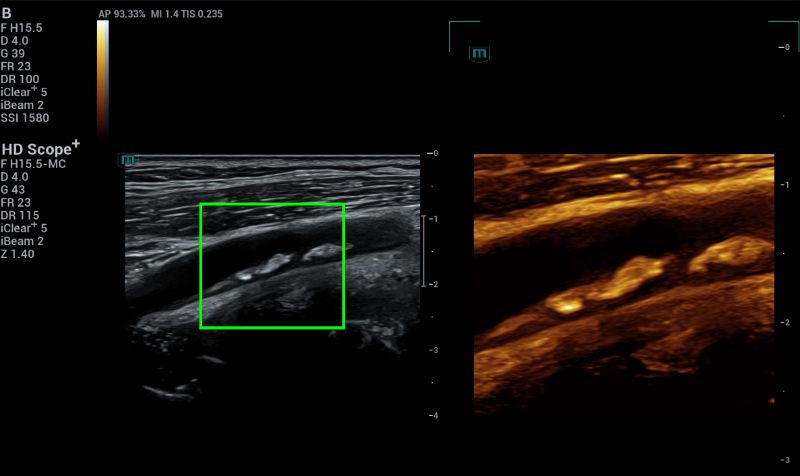

HD Scope+ improves spatial and contrast resolution, allowing for clearer differentiation of tissue types (Fig 5). This can reveal the complex nature of a plaque, including echogenicity, heterogeneous elements, and lucent cores, which are important for determining its stability and risk.

B mode HD Scope+ on the plaque to evaluate the plaque morphology.

Fig.5: B mode HD Scope+ on the plaque to evaluate the plaque morphology.